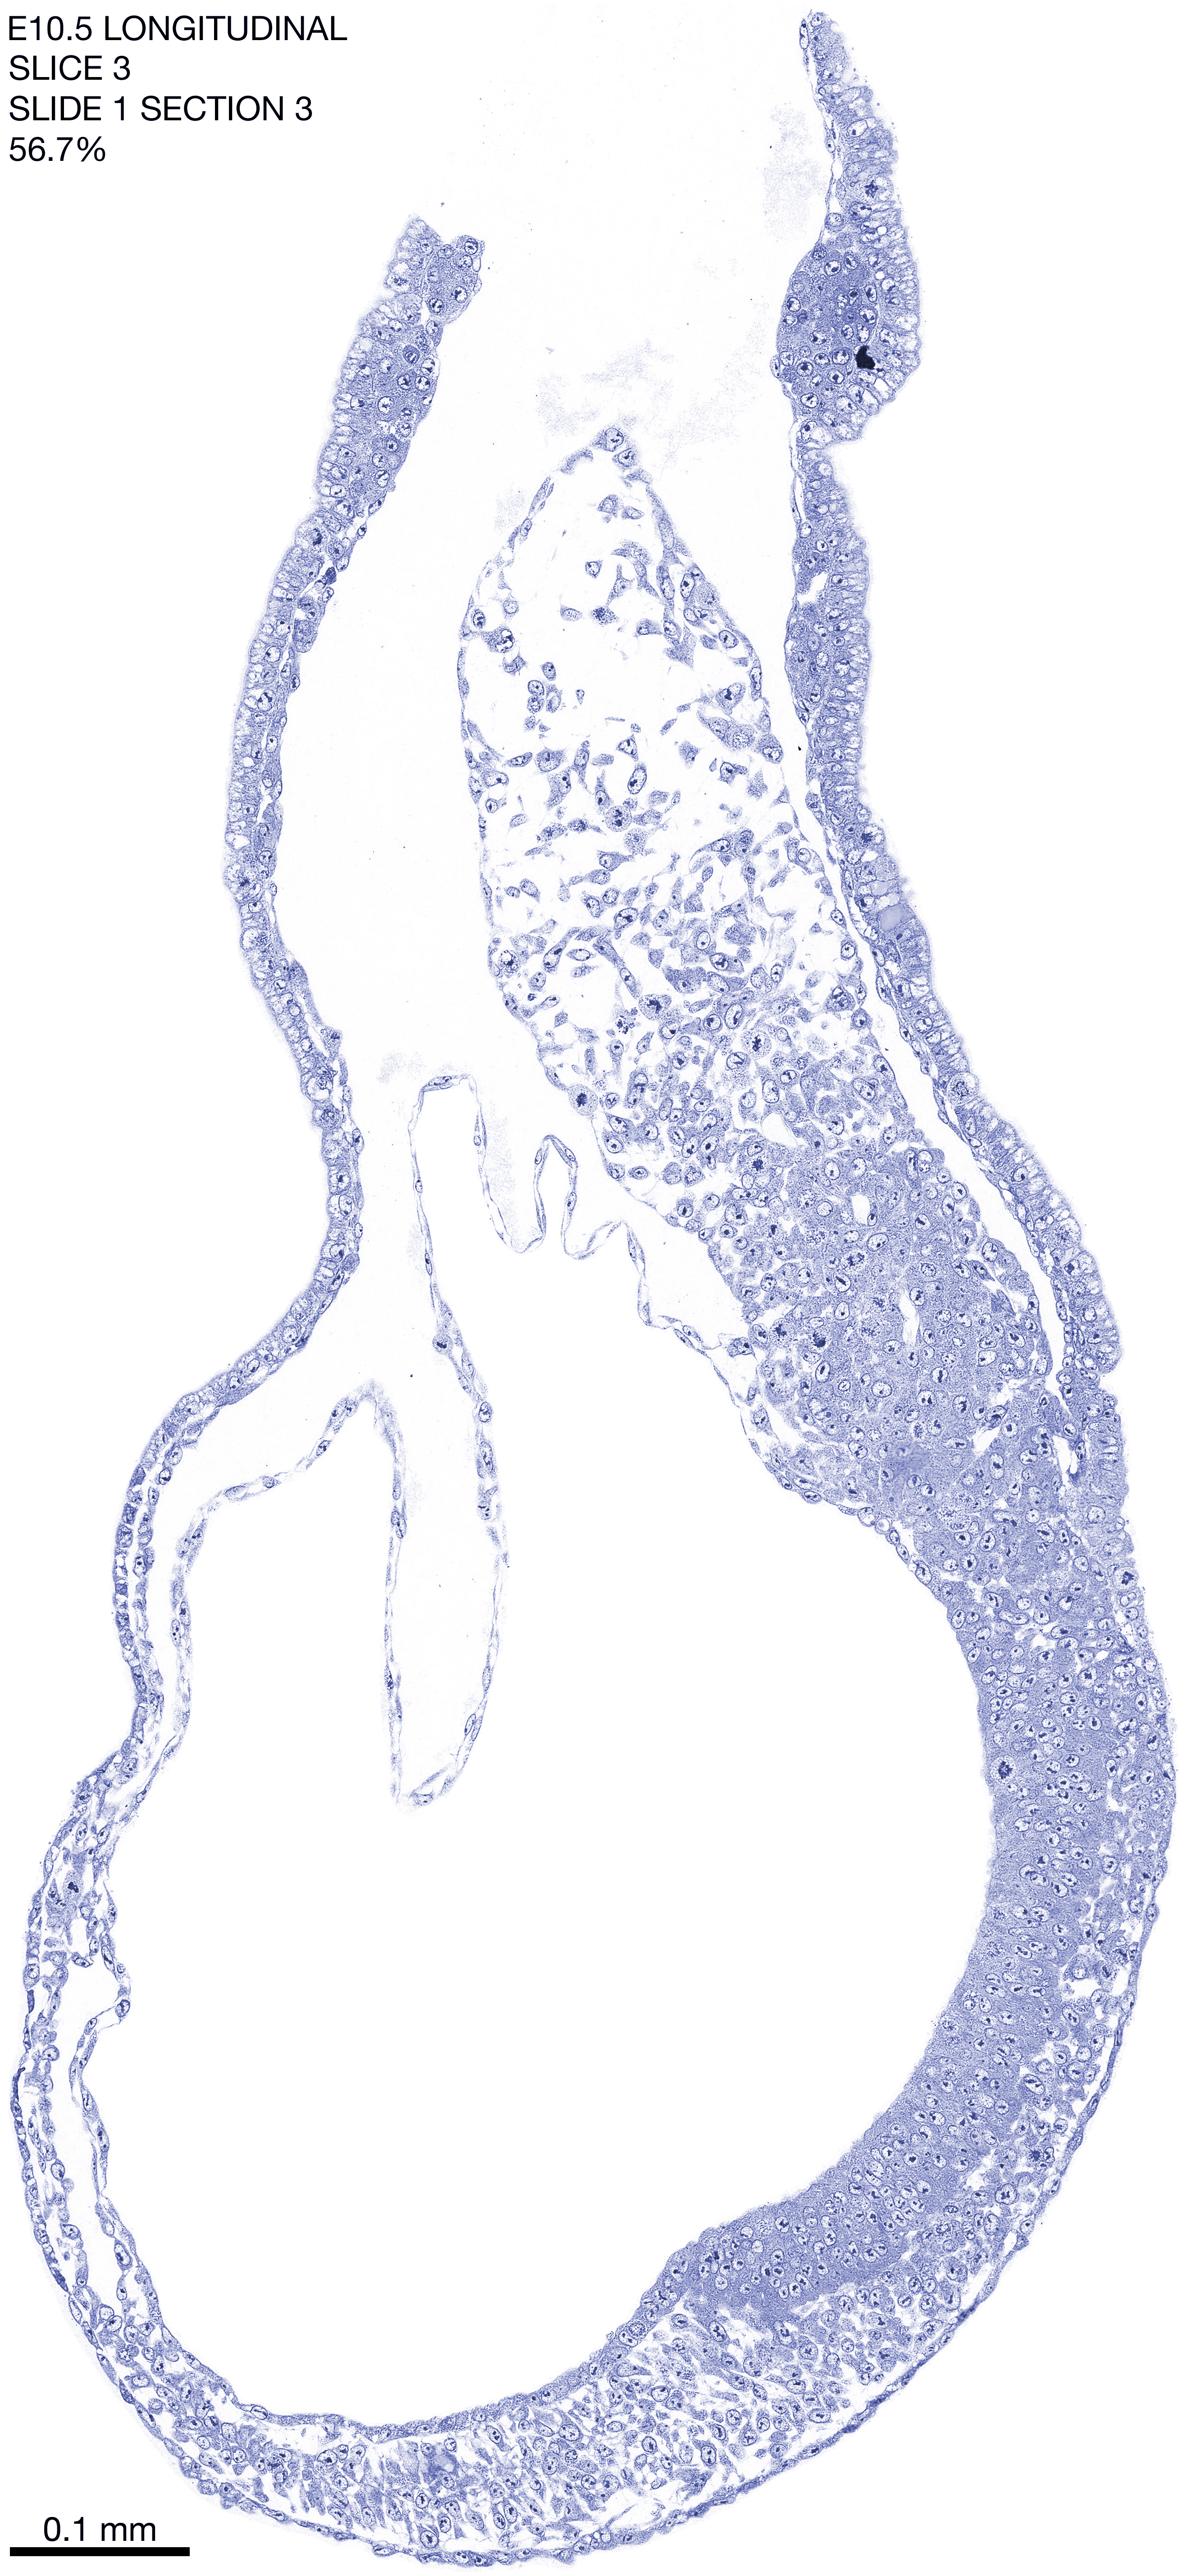

E10.5 Longitudianal Archive This page contains jpg files of ALL SLICES (each 3µm thick) that were scanned of the E10.5 longitudinally cut specimen. Download: Large | High Res Download: Large | High Res Download: Large | High Res Download: Large | High Res Download: Large | High Res Download: Large | High Res Download: Large | High Res Download: Large | High Res Download: Large | High Res Download: Large | High Res Download: Large | High Res Download: Large | High Res Download: Large | High Res Download: Large | High Res Download: Large | High Res Download: Large | High Res Download: Large | High Res Download: Large | High Res Download: Large | High Res Download: Large | High Res Download: Large | High Res Download: Large | High Res Download: Large | High Res Download: Large | High Res Download: Large | High Res Download: Large | High Res Download: Large | High Res Download: Large | High Res Download: Large | High Res Download: Large | High Res Download: Large | High Res Download: Large | High Res Download: Large | High Res Download: Large | High Res Download: Large | High Res Download: Large | High Res Download: Large | High Res Download: Large | High Res Download: Large | High Res Download: Large | High Res Download: Large | High Res Download: Large | High Res Download: Large | High Res Download: Large | High Res Download: Large | High Res Download: Large | High Res Download: Large | High Res Download: Large | High Res Download: Large | High Res Download: Large | High Res Download: Large | High Res Download: Large | High Res Download: Large | High Res Download: Large | High Res Download: Large | High Res Download: Large | High Res Download: Large | High Res Download: Large | High Res